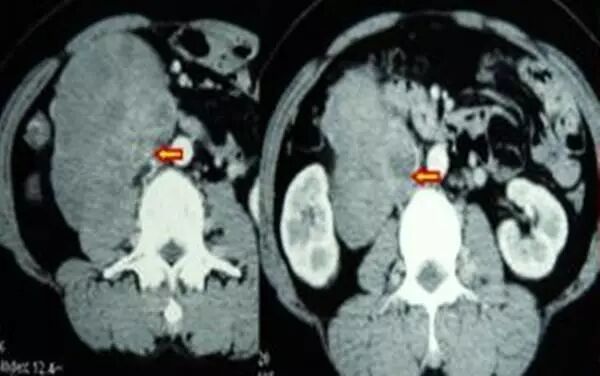

3、 大血管疾病:主动脉狭窄和夹层,腹主动脉瘤的开放手术和腔内人造血管隔绝术。大动脉炎累及内脏血管病变的处理。上下腔静脉闭塞和狭窄的腔内成型和布加综合征的根治术。肝硬化门脉高压的腔内分流术和脾功能亢进栓塞治疗。

4、内脏血管性疾病:肠系膜动脉和肾脏动脉的狭窄和栓塞的腔内治疗。

主动脉夹层的介入治疗